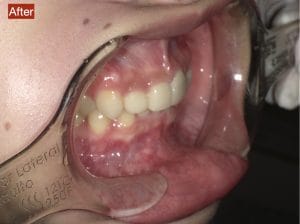

Case033

前歯が虫歯なのと、保険のプラスチックで大きく治療されていて色が悪いこと、歯並びが出っ歯気味であることを気にしてセラミックにしたいという主訴で来院された患者様です。

虫歯が大きかったところは神経治療をきちんと行い、

初診時を含めてトータル4回のご来院で完了です。

今回は前歯を下げる、歯列を整える、白すぎず自然に綺麗に見える色というご希望に沿って治療しました。

ご興味のある方はいつでもご相談ください。

担当 理事長 佐藤 悠野